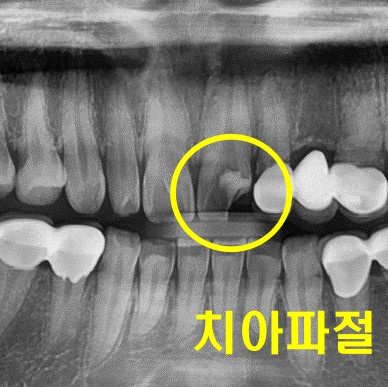

예시 사진을 보면 앞니에

치아 파절이 생긴 것으로 보여집니다.

앞니는 외부 충격에 약하기 때문에

넘어질 때 충격으로 인해

앞니가 깨지는 경우도 있습니다.

상기 예시 사진은 큰 파절로

확인되기 때문에

신경치료를 진행해야 할 것으로 판단됩니다.